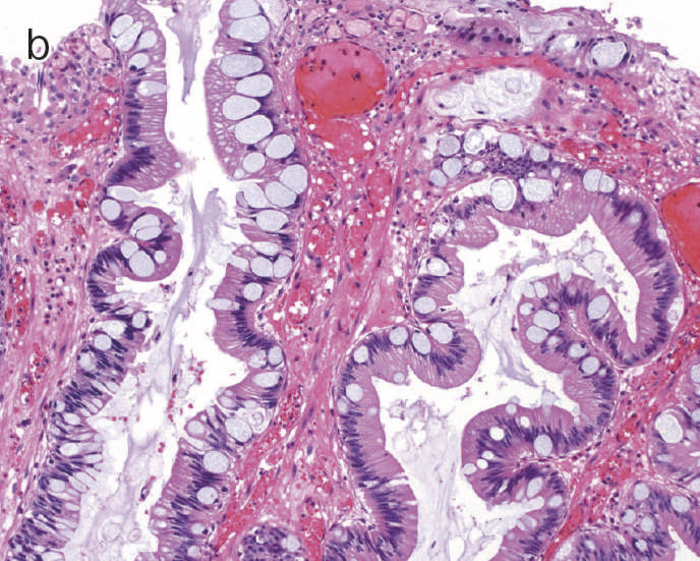

図10 Dysplasiaの多様な組織像

- 表層分化を示すdysplasia。

- 分泌顆粒の局在が核上,核下,表層と不規則な分布を示すdystrophic goblet cellを含むdysplasia。

- UC関連粘膜内低分化腺癌:粘膜内において粘液癌あるいは印環細胞癌が認められる。

- cの拡大像。